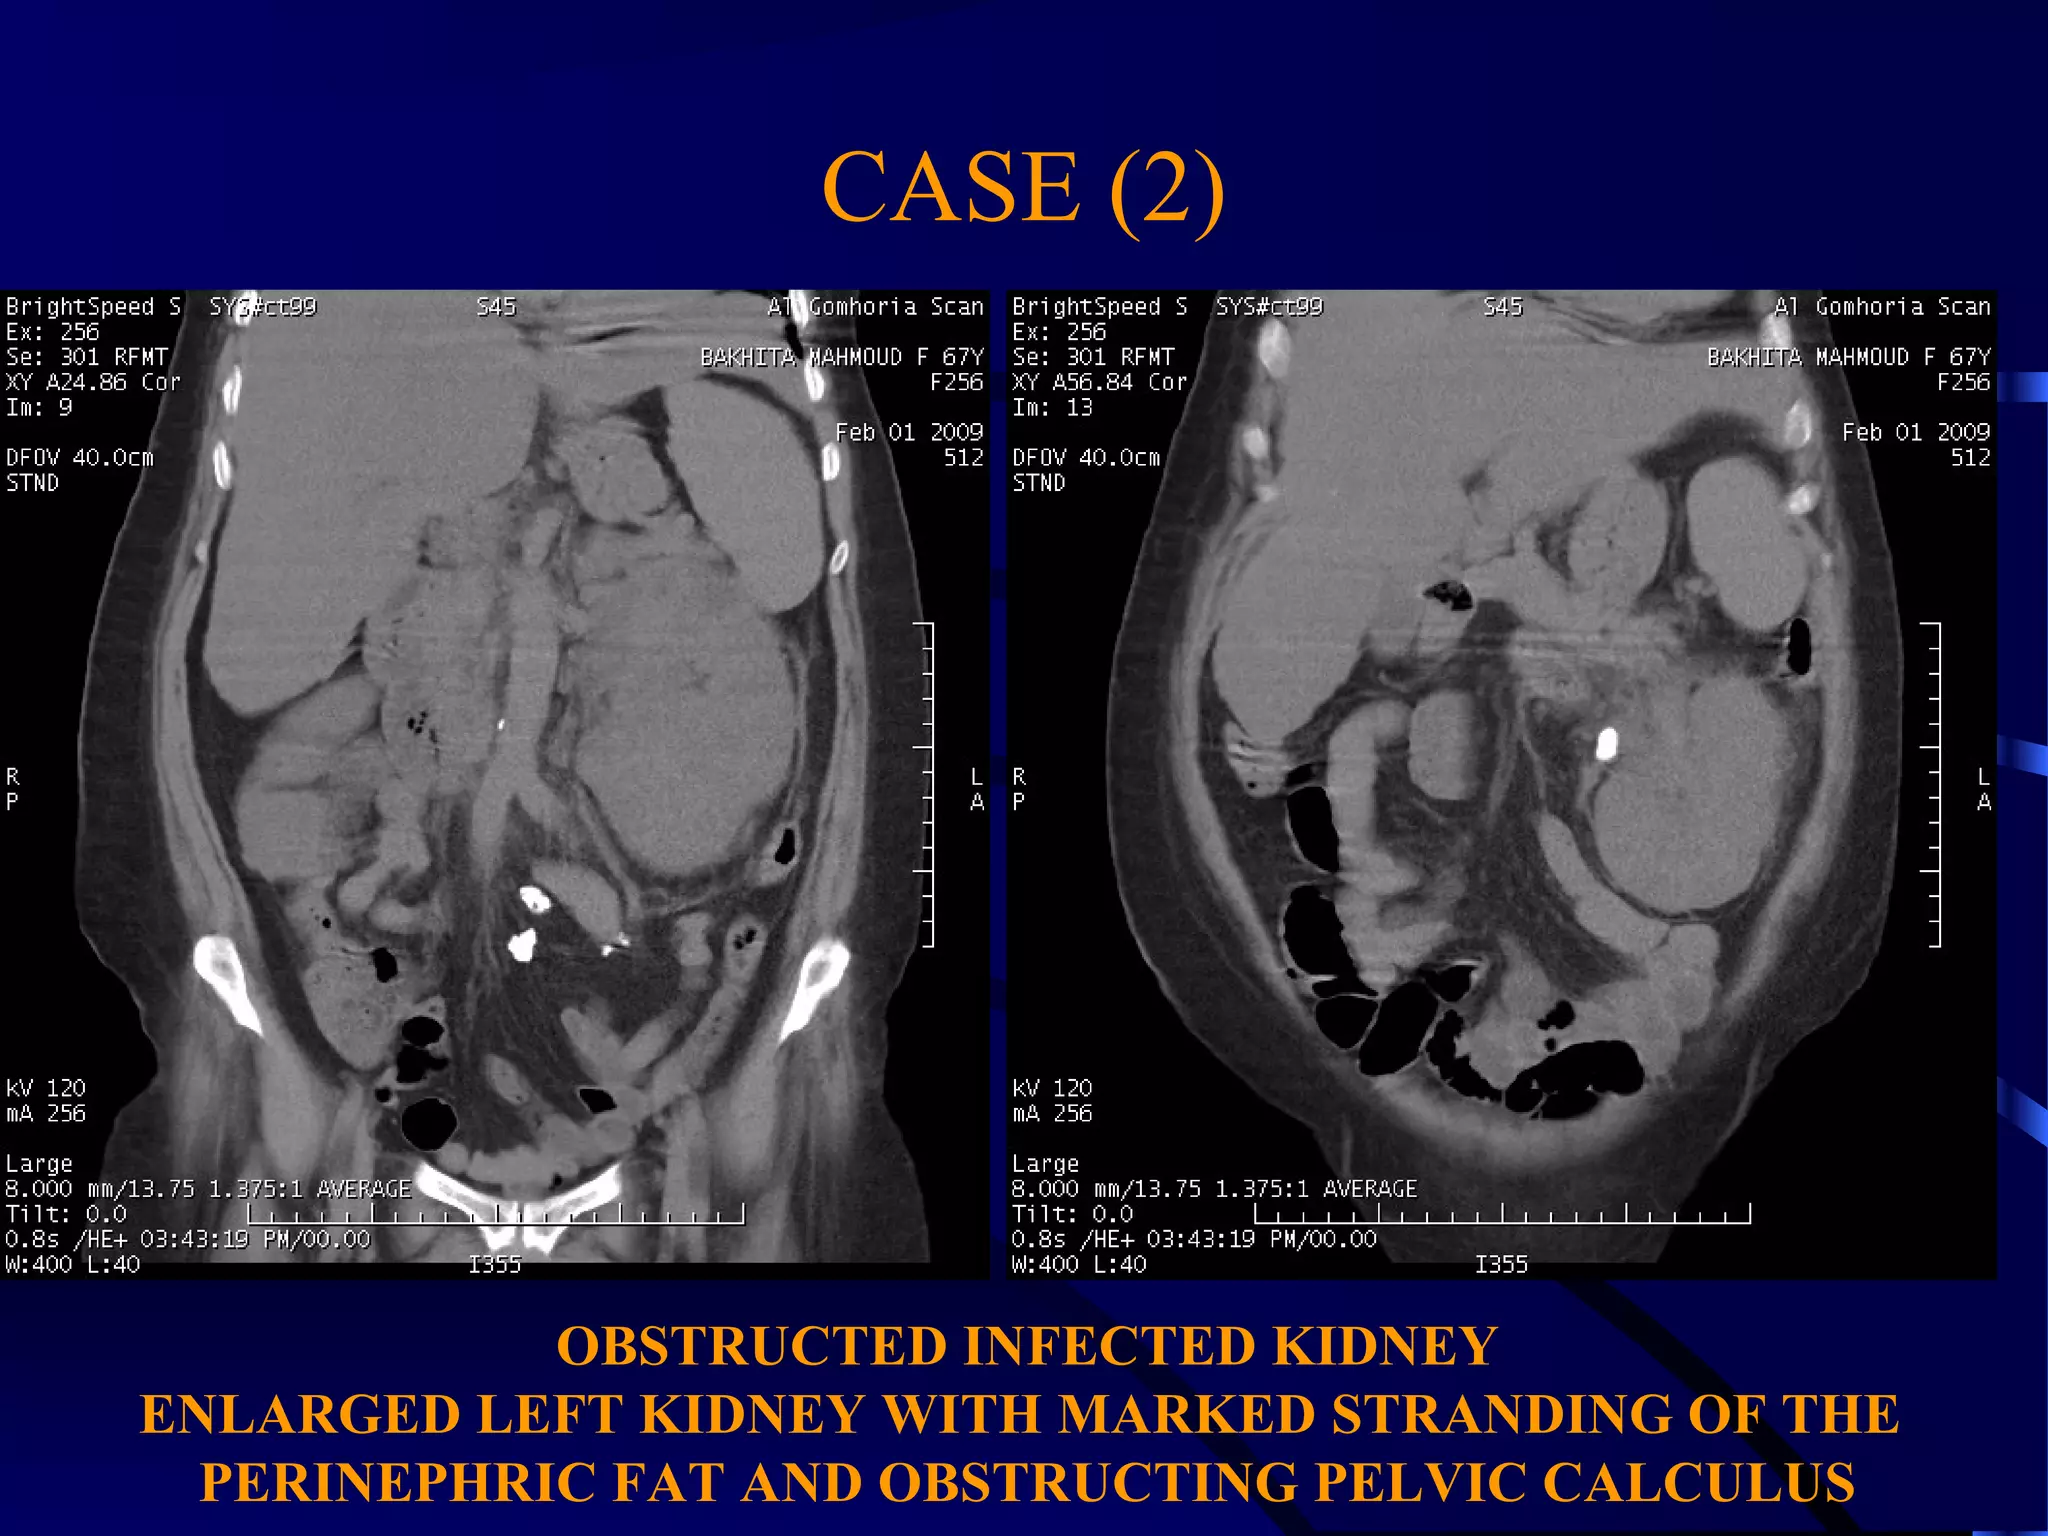

CASE (2)

OBSTRUCTED INFECTED KIDNEY

ENLARGED LEFT KIDNEY WITH MARKED STRANDING OF THE

PERINEPHRIC FAT AND OBSTRUCTING PELVIC CALCULUS